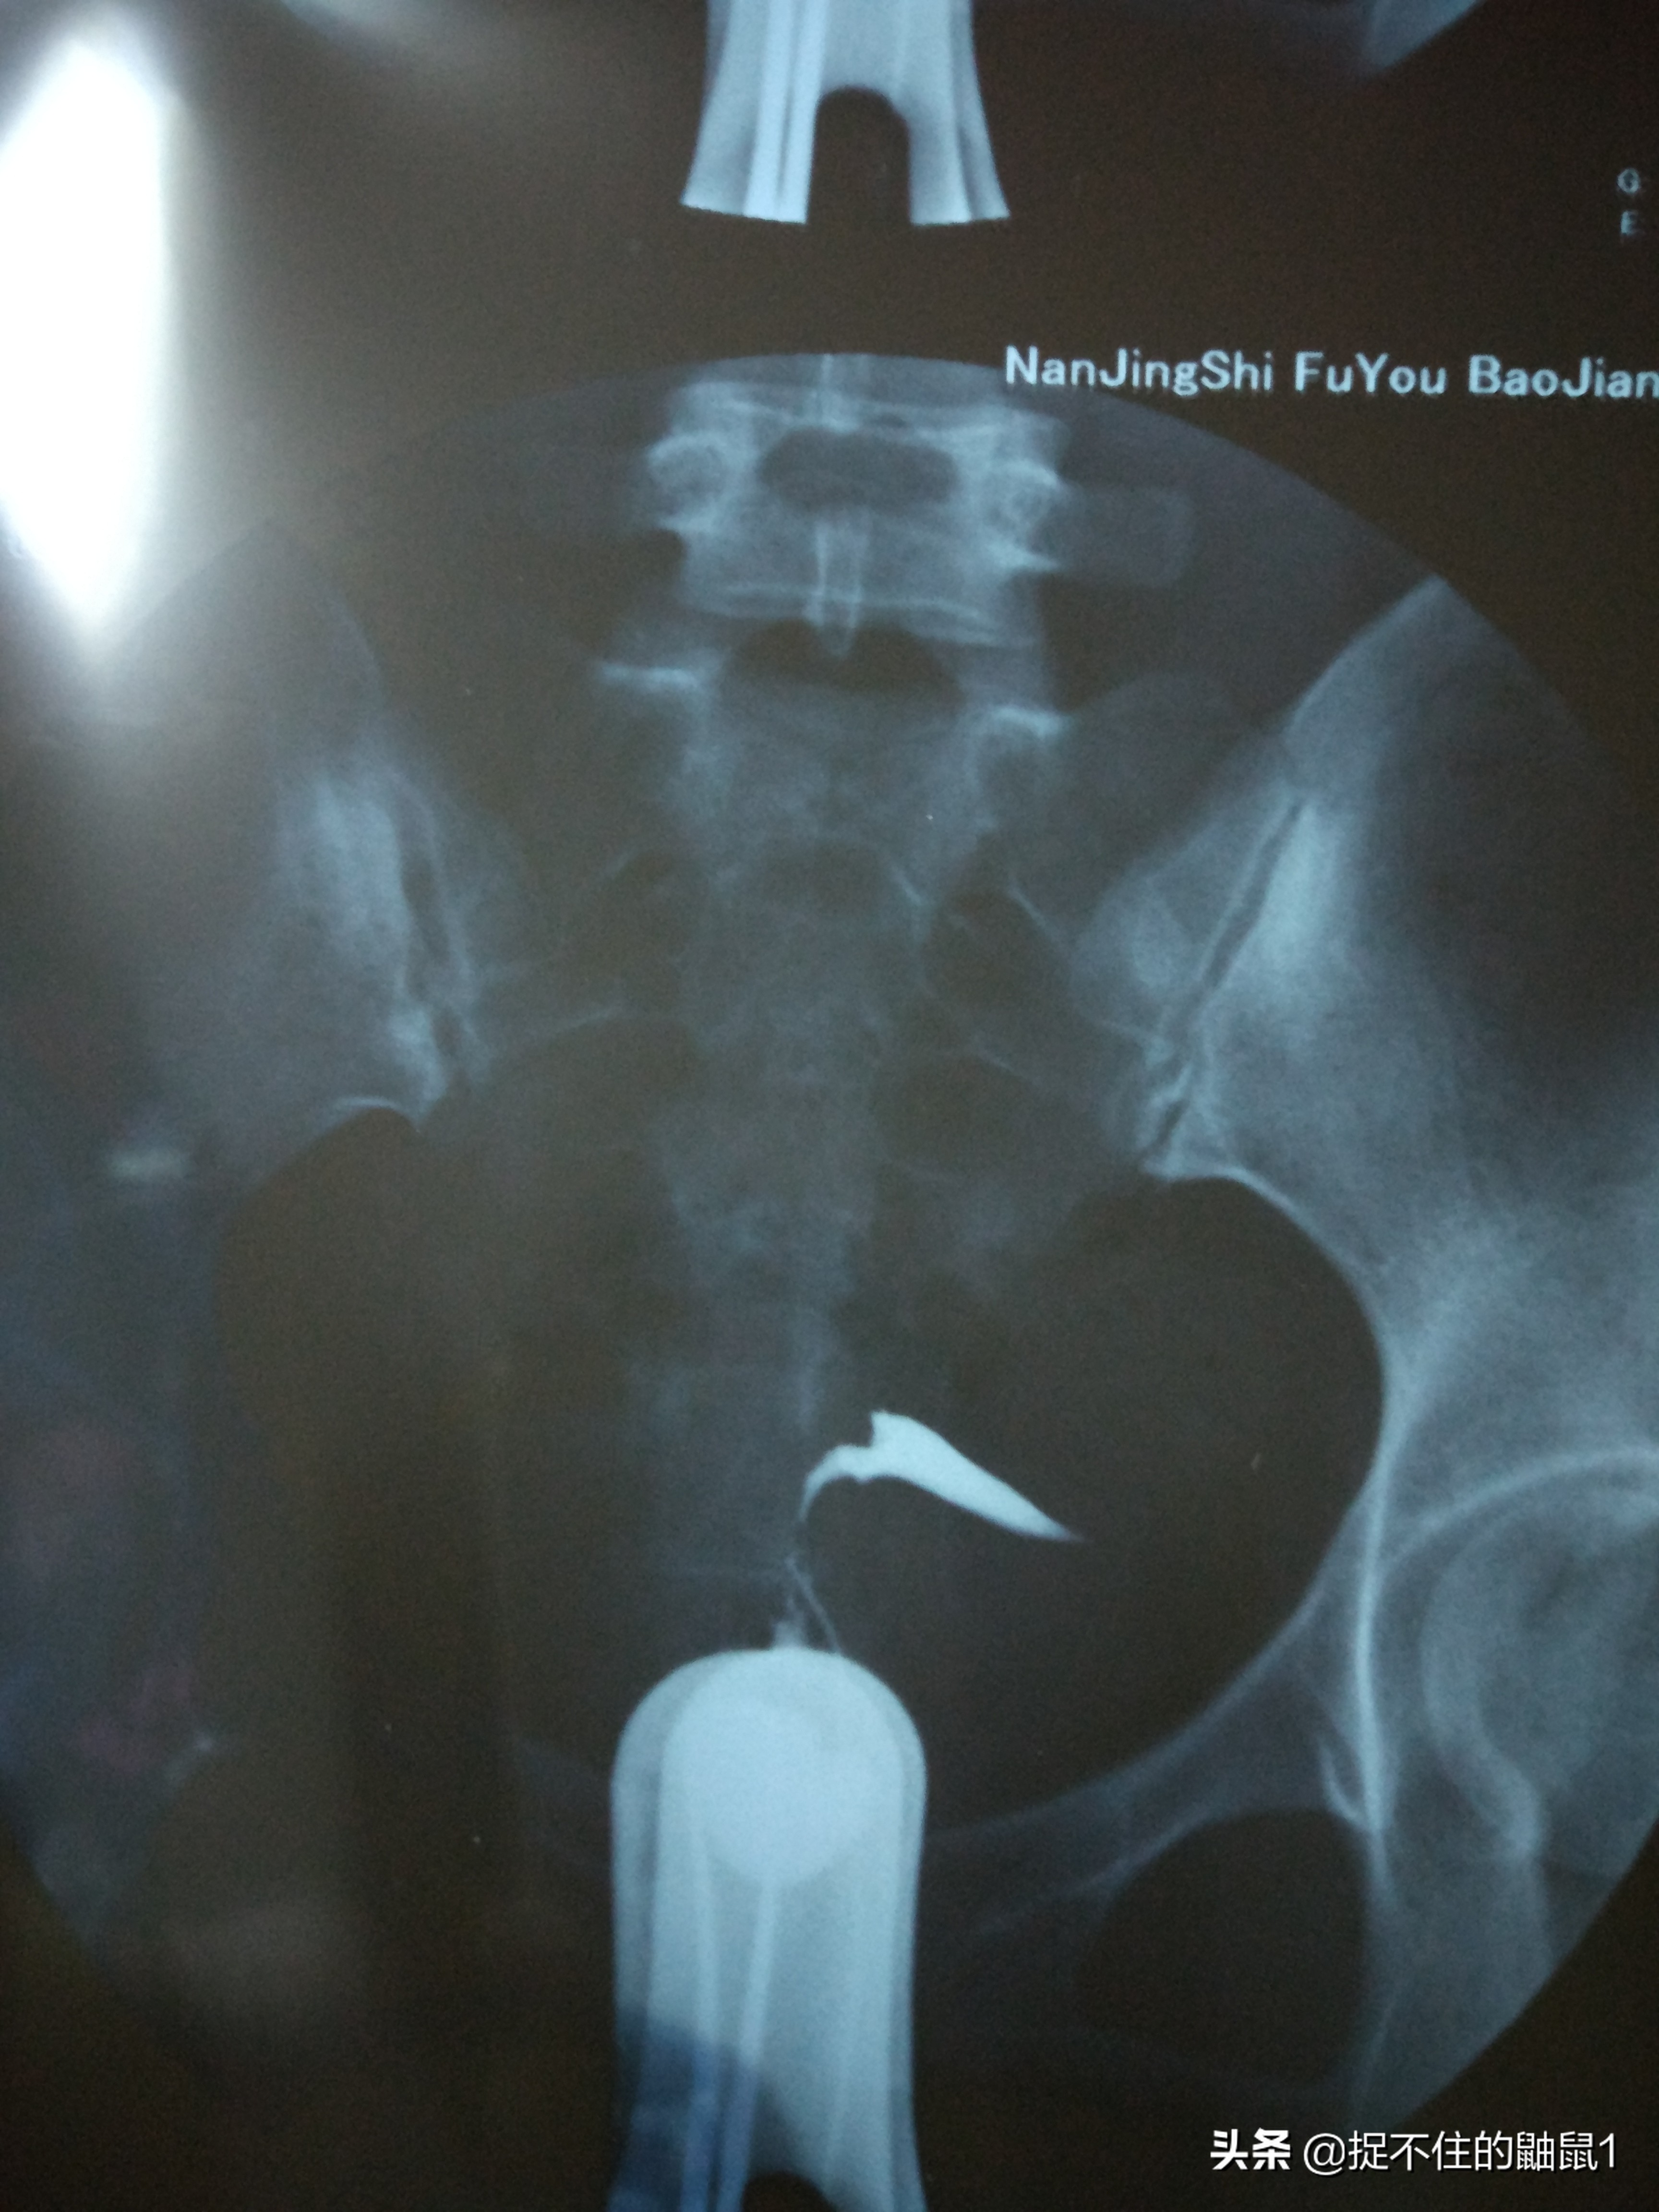

这是造影片子,发亮的是碘油,这是推入当天的造影

这是第二天碘油弥散后的造影,没弥散开,就是输卵管不通,这是医生跟我说的,我也看不懂